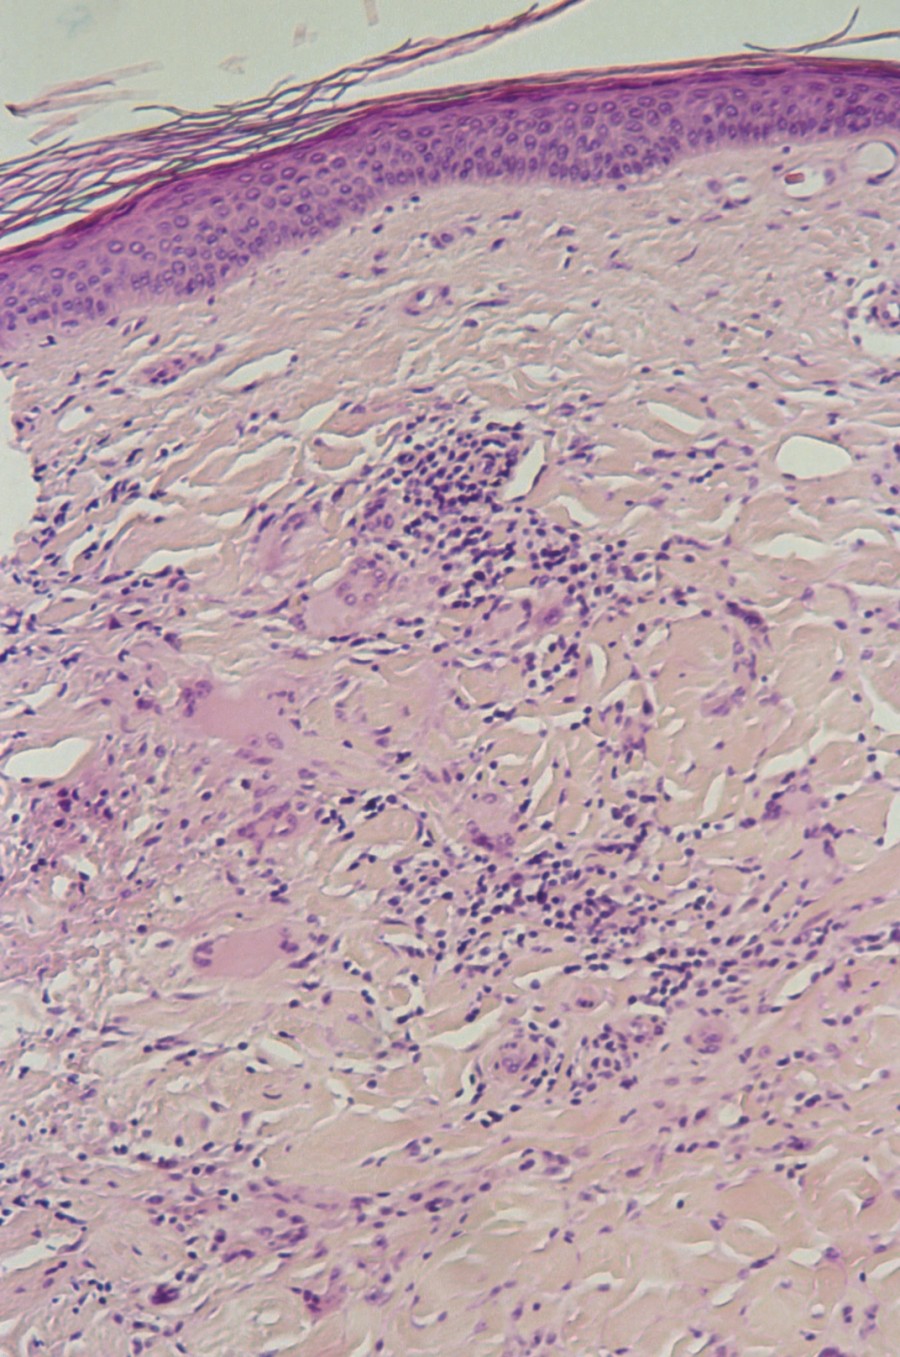

rand en een atrofisch gehypopigmenteerd centrum. Histologisch ziet men solaire

elastose en multinucleaire reuscellen.